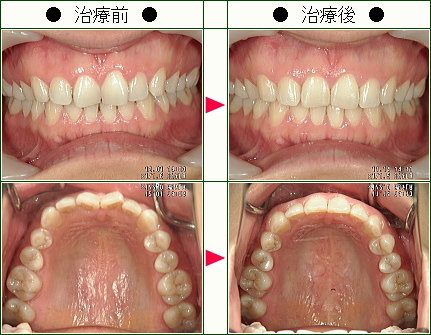

☆歯のデコボコ矯正症例(甲斐様 38歳 女性)